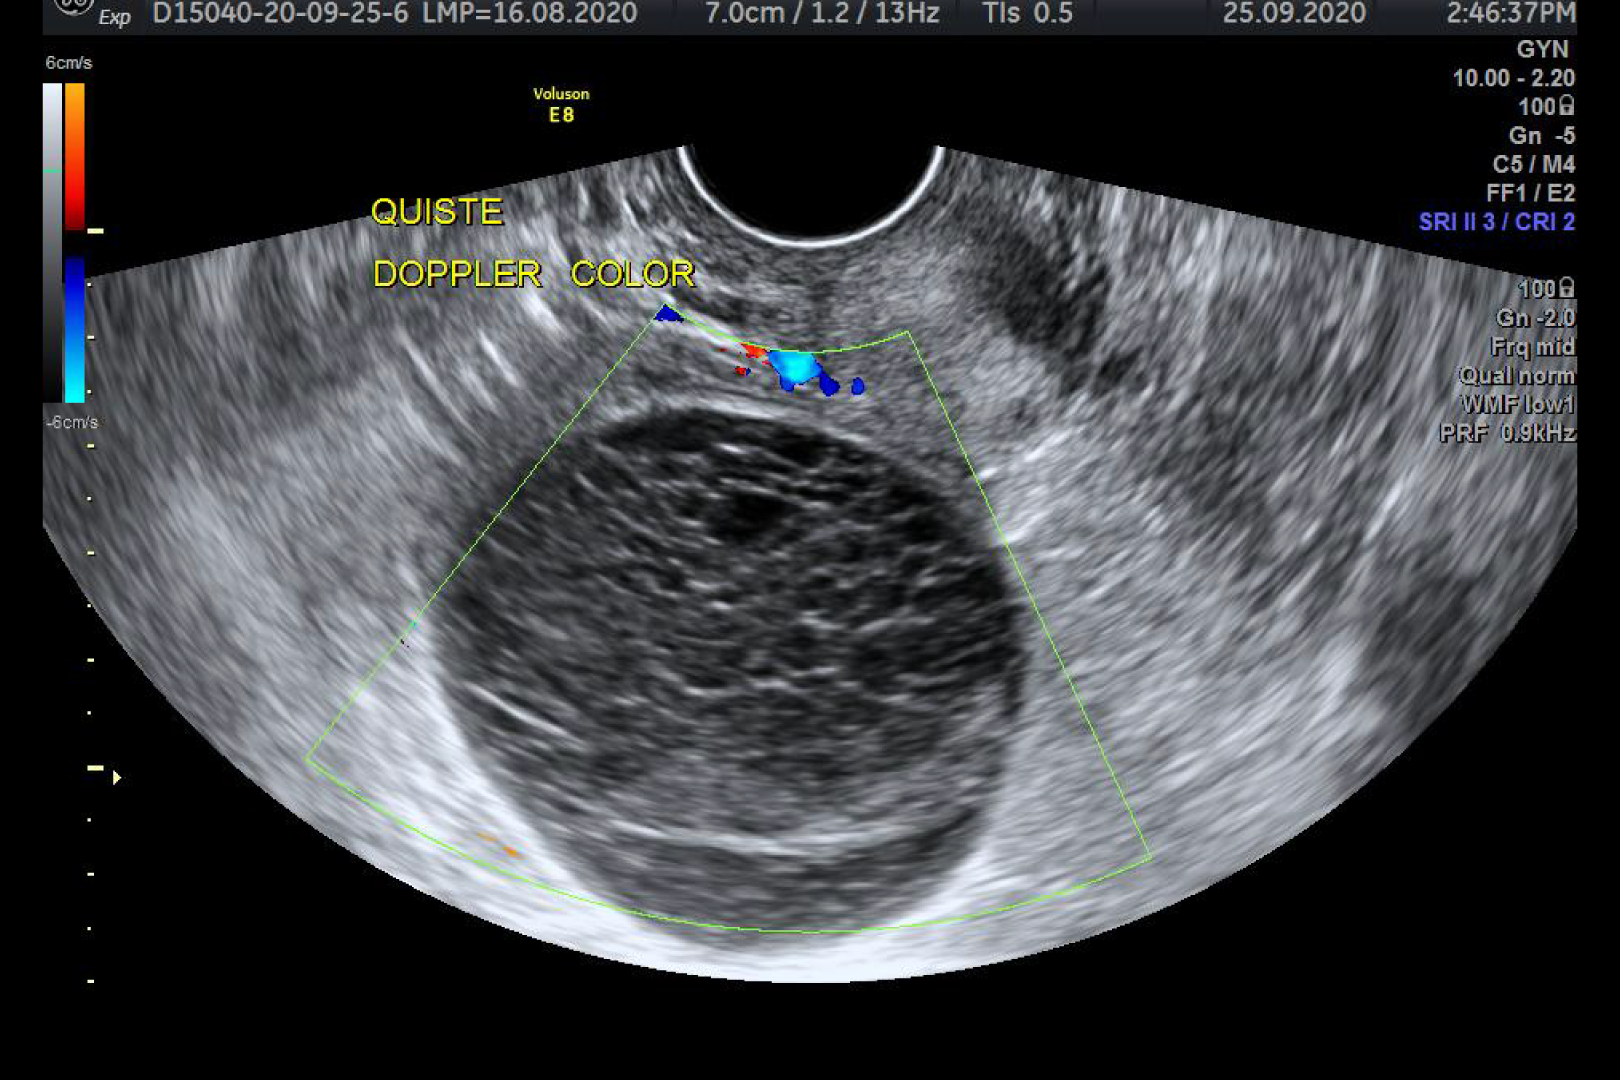

HD Live quinta dimensión, Imágenes de volumen con profundidad y claridad, que aportan un realismo anatómico para un mejor diagnóstico.